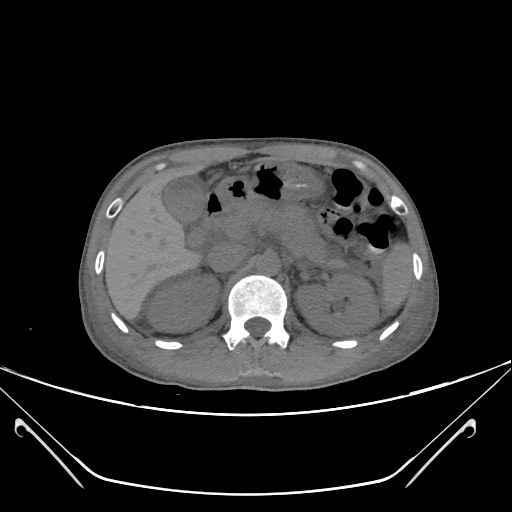

【全腹CT平扫】:急性胰腺炎:胰腺肿胀,胰周渗出、少许积液,局部肠系膜浑浊,双侧肾周筋膜增厚,双侧结肠旁沟及盆腔少许积液。